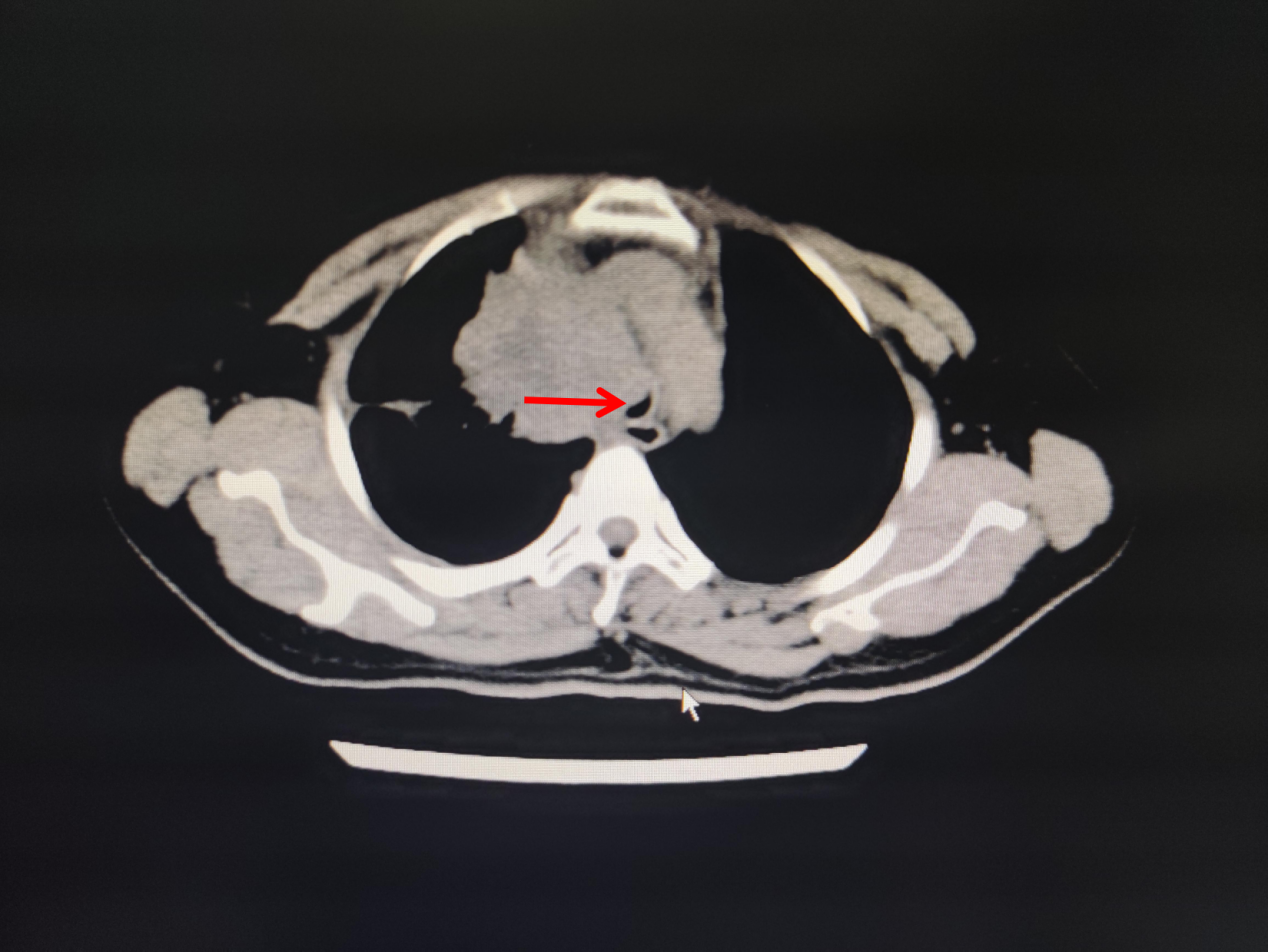

今年57岁的蔡女士,因晚期肺癌住院,肿瘤压迫气管导致气管严重狭窄,住院期间突发呼吸困难,伴烦躁不安、大汗淋漓,紧急行气管插管接呼吸机辅助通气,送ICU抢救。无独有偶,这边ICU医生正在积极抢救蔡女士,那边医院急诊科又打电话说急诊室有一名呼吸困难的患者需要紧急插管。这也是一名肿瘤压迫气管导致气管狭窄的患者,胸部CT可见气管中下段显著性狭窄,患者呼吸困难已近1周,今天突然加重,喘憋、口唇紫绀,ICU翁医生马上紧急予以气管插管,呼吸机持续性辅助通气。

图1.林某某CT 图2.蔡某某CT图片